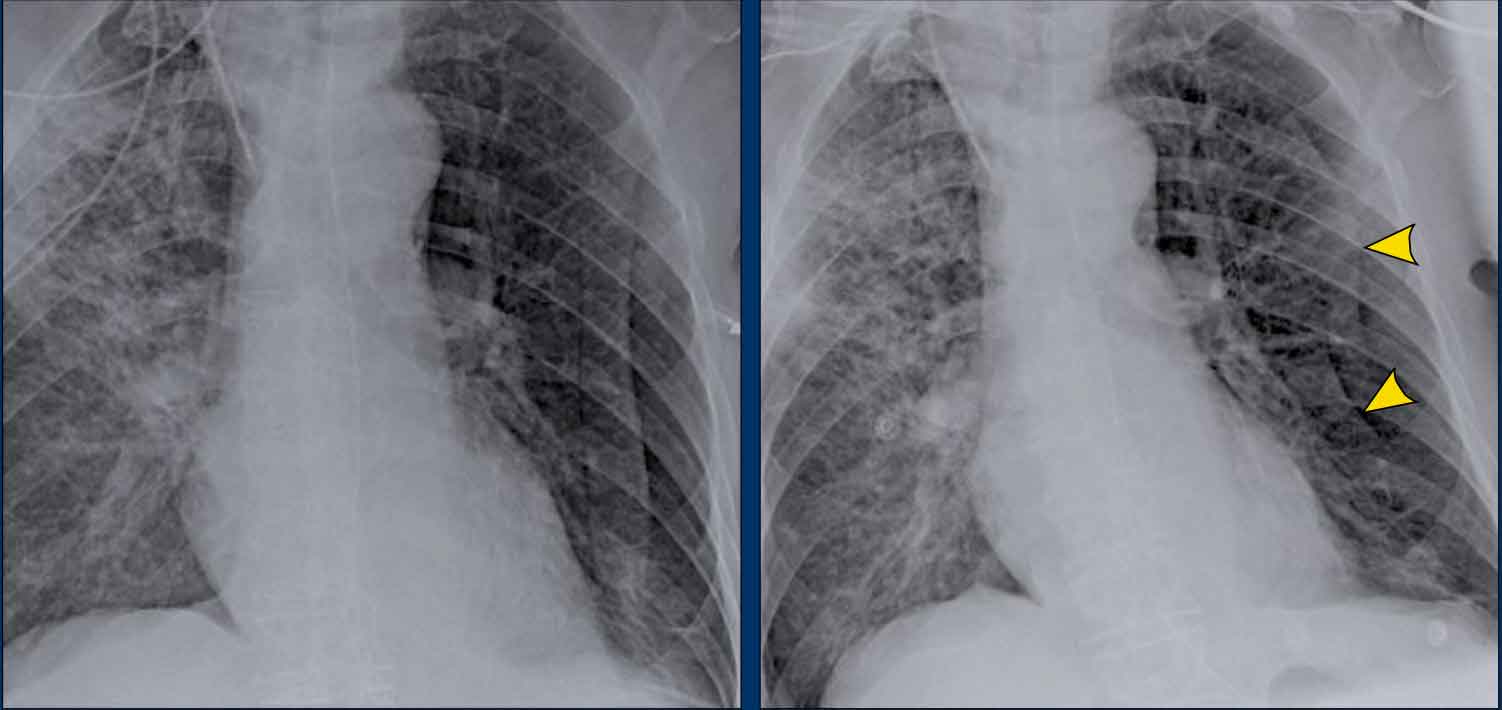

Case Example: Subtle Signs of Congestive Heart Failure

Begin by reviewing these current chest radiographs.

Based solely on these images, one might suspect congestive heart failure (CHF), though the findings are subtle.

Now review the previous study…

Scrolling between the current and prior films significantly increases diagnostic confidence in your diagnosis of congestive heart failure.

Key comparative findings include:

• Cardiac size: Slightly increased compared to the previous study; however, cardiomegaly was already present.

• Pulmonary vasculature: Mild vascular engorgement suggesting elevated pulmonary venous pressure.

• Interstitial markings: Subtle signs of interstitial edema .

• Pleural effusions: Bilateral small effusions, with subtle changes in the inferoposterior borders of the lower lobes, suggesting fluid accumulation.